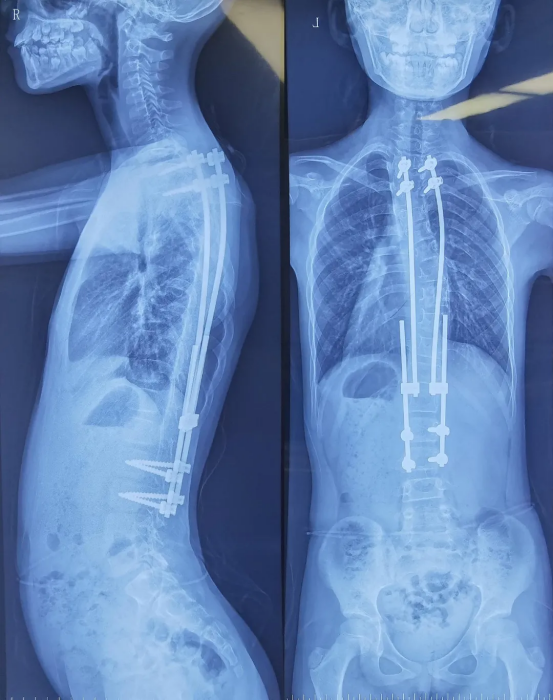

Fluoro-verified precise screw implantation

Preoperative imaging of the pediatric patient